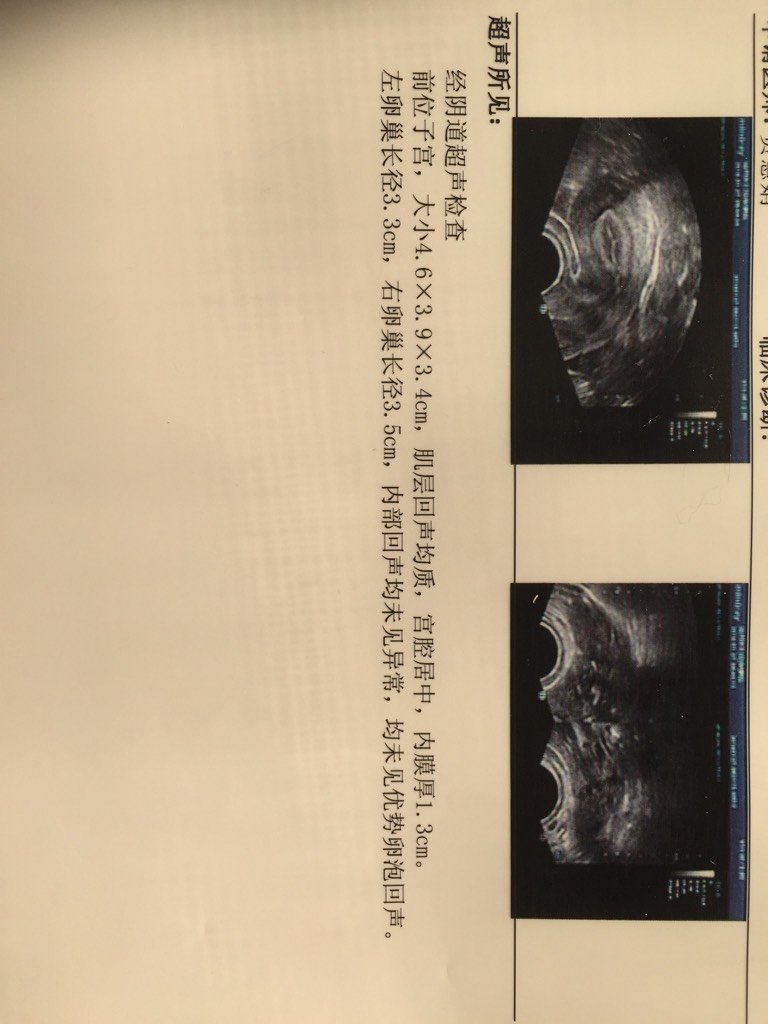

今天去做的卵泡监测,月经第18天,无优质卵泡,帮我看看 今天去做的卵泡监测,月经第18天,无优质卵泡,帮我看看 点击展开 接好孕🐒宝宝 2016-01-27 12:00 为您推荐: 其他回答 已经排了吧 炚睿妈咪 2016-01-27 17:02 相关问题 本人是一月15来的月经,今天月第18天,监测卵泡只有一个1 2·0 7的卵泡,子宫内膜0 7,这样 我准备生二胎,可是备孕了快1年了,都没怀上,我今天月经第1天,做了B超竟然还有卵泡7×5mm,6× 27号月经,8号体外射精,12号早上10点B超时卵泡还是20*18,13号早上10点去B超就显示已